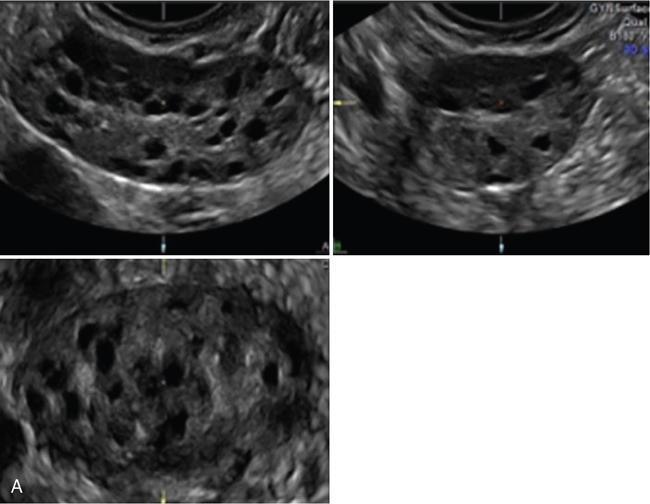

3. 3. 3D manual mode – reproducibility is better compared with 2D methods (Fig. 11.20.1.3).

• Allowing the use of rendering mode with thin slice, on contrast enhancement, making it easier to identify follicles

Image

Fig. 11.20.1.3 (A) 3D multiplanar mode without vocal contrast imaging (VCI). (B) 3D multiplanar mode with vocal contrast imaging (VCI).